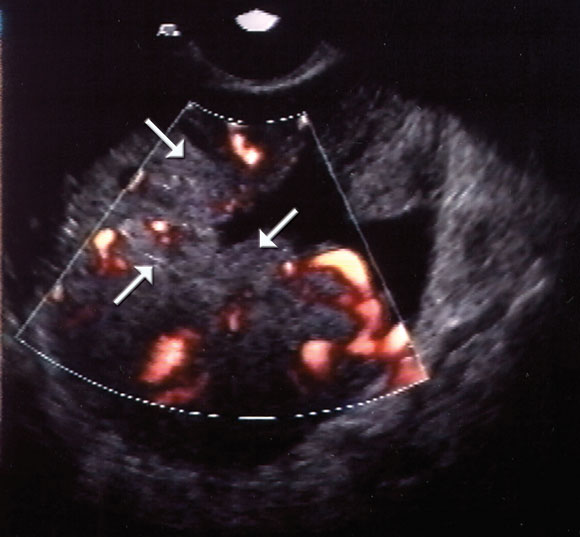

A number of screening tests have been evaluated or are being evaluated currently. These include bimanual pelvic examination, ultrasound examination (Box), with or without colour Doppler flow imaging, and measurement of various circulating proteins.

Ultrasound examination alone has neither sufficient specificity nor sufficient predictive value to justify its use in community screening, and it is expensive. It is currently not known whether the addition of Doppler flow imaging substantially improves the sensitivity of ultrasound alone.3